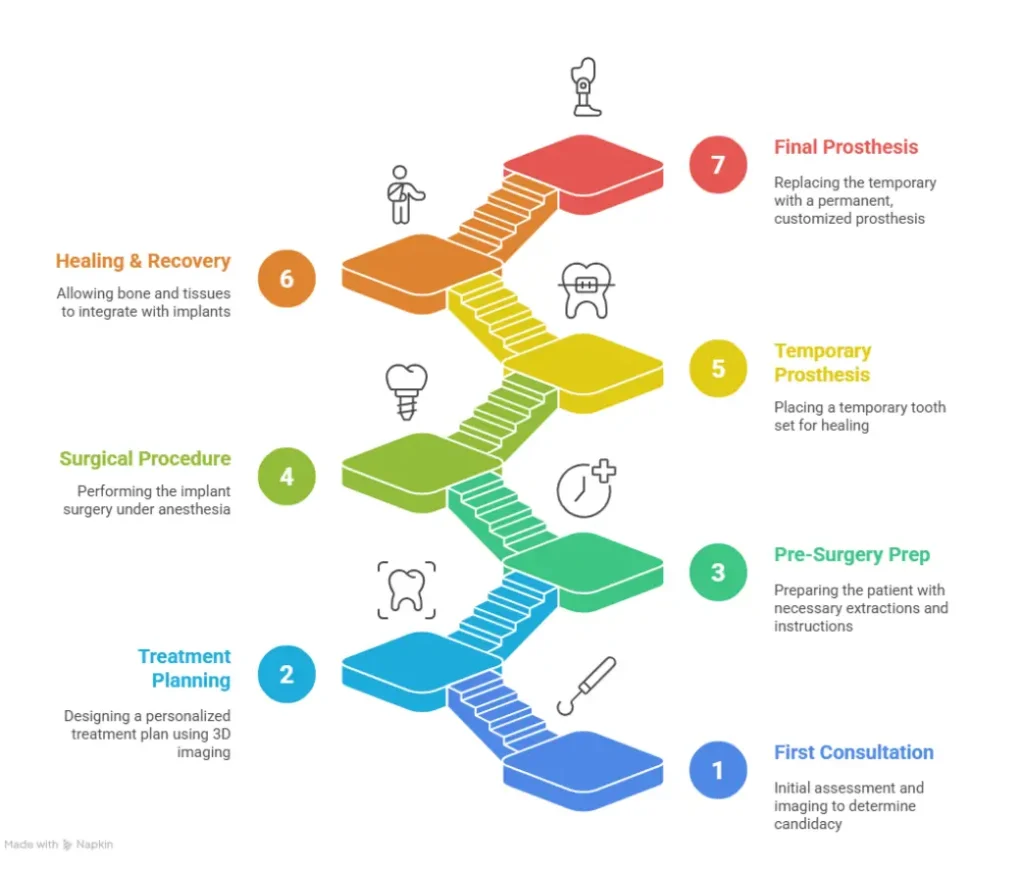

The process of getting Zygomatic dental implants involves a few steps before the actual procedure. These are what they are:

Step 1. Your First Consultation

Your dentist will check on your medical history, conduct a comprehensive oral examination, and take advanced CT imaging to evaluate bone structure. This determines whether you qualify as a candidate and helps plan the surgery.

Step 2. Treatment Planning

By employing 3D digital imaging, dental experts design a plan suited to your treatment needs. Planning will allow dental specialists to set the number of implants, placement sites, and prosthesis types.

Step 3. Pre-Surgery Prep

Rare cases employ Oral Surgery where teeth are extracted to accommodate the planned procedure. The dental expert will guide you on pre-operative care, fasting, and cessation of medications.

Step 4. Surgical Procedure

Implants require the patient to be put under local or general anesthesia. Based on the specifications, additional implants may need to be laid in the upper jaw’s front row.

Step 5. Placement of Temporary Prosthesis

Dentists will fix a temporary tooth set on the implant during surgery. It’s a step that helps healing and gives patients a functional smile.

Step 6. Healing & Recovery

Although already stable, your bone and tissues require additional time to heal and integrate with the implants through a process called osseointegration. The whole process usually takes between 3 and 6 months for a full mend.

Step 7. Placing the Final Prosthesis

When healing is adequate, it’s time to remove and replace the temporary prosthesis with a customized permanent one. The final prosthesis is long-lasting and durable, delivering confidence and functionality.